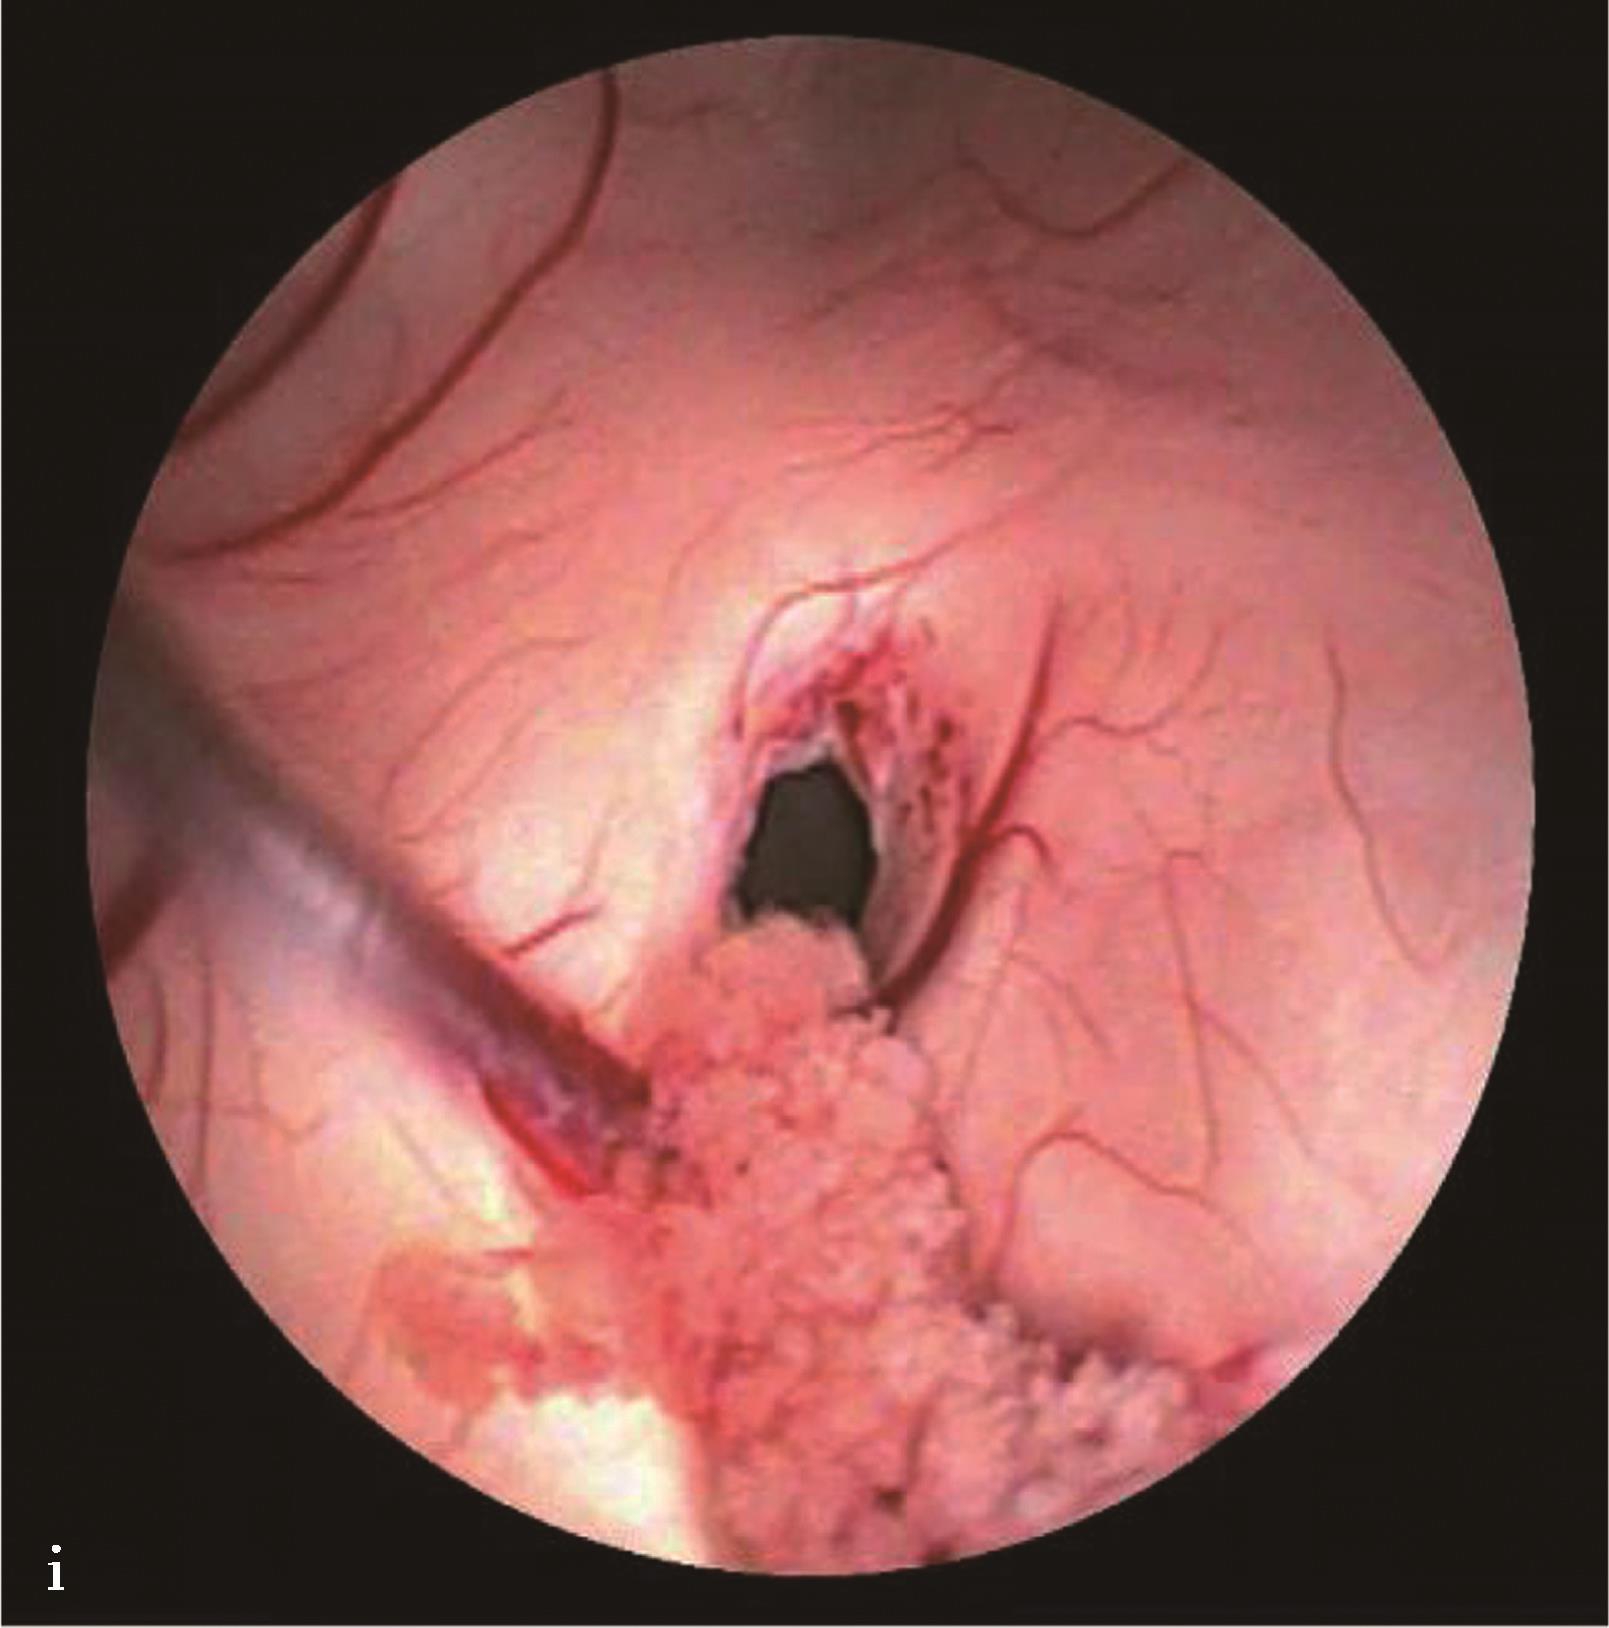

图3-1-1-4 感染后脑积水内镜下探查所见

a.脑室壁上的菌斑;b.脑室内结核所致干酪样坏死物;c.脑室内真菌感染;d.第四脑室内囊虫